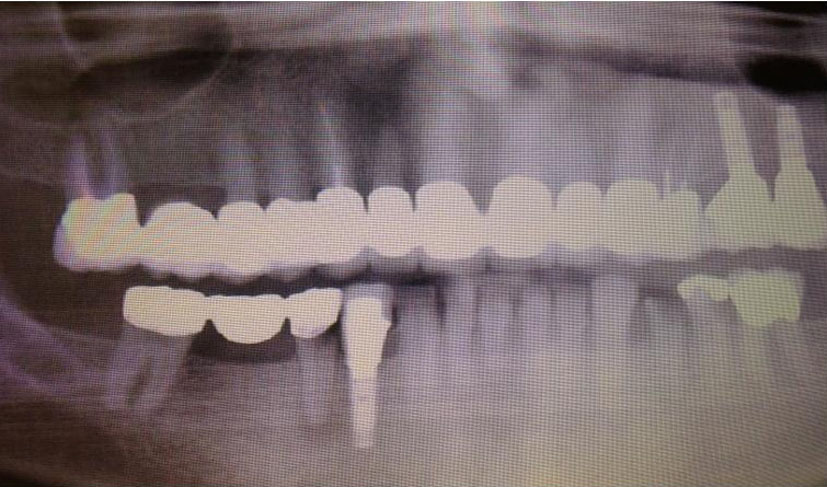

She received radiation to her left orbit, L5 sacrum and T2-T5 vertebrae. Both zoledronic acid and denosumab were continued. However, patient developed osteonecrosis of her jaw (ONJ) secondary to bisphosphonates (Fig. 11). A dental consultation was obtained and both zoledronic acid and denosumab were stopped.

![]() Click for large image | Figure 11. Osteonecrosis of the jaw (ONJ) secondary to bisphosphonates. |